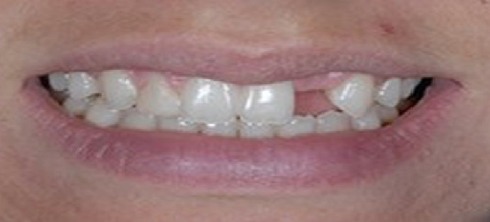

A 26-year-old female with severe crowding. Comprehensive orthodontic treatment was completed. Patients were amazed by the results.